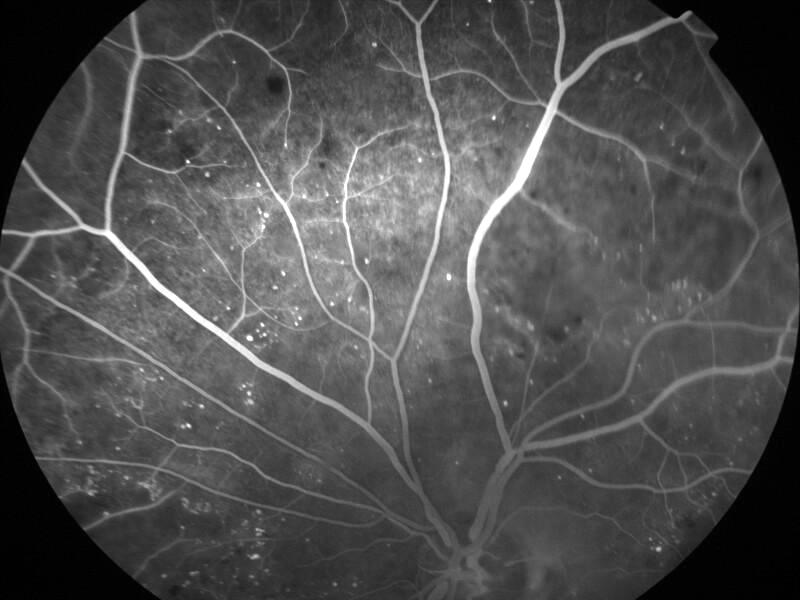

rétinopathie diabétique pré-proliférante

IM000022.jpg